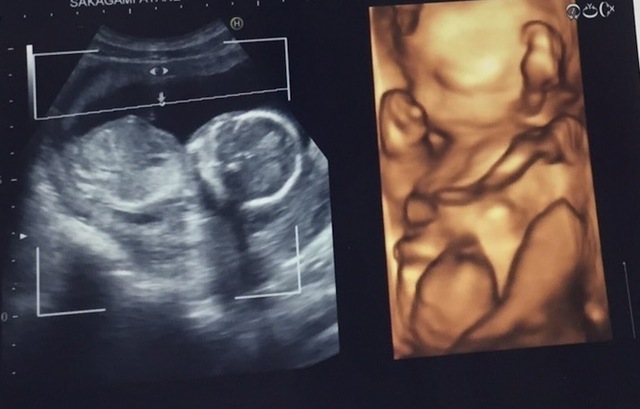

15週6日(15w6d・男の子)|ぷるぷる姫 さん(33歳)

エコー写真撮影時のエピソード:

顔が見えたとき。手で顔を触って、撫でているようで、すごく愛おしく感じました。今まで2Dの画像のみだったのが、3Dで顔の形、手の形が見え、お腹の中で育っていく様子を感じることが出来ました。

発育過程は教科書的には十分理解していますが、自分のお腹の中でその過程が進んでいるのはとても不思議な気持ちでした。